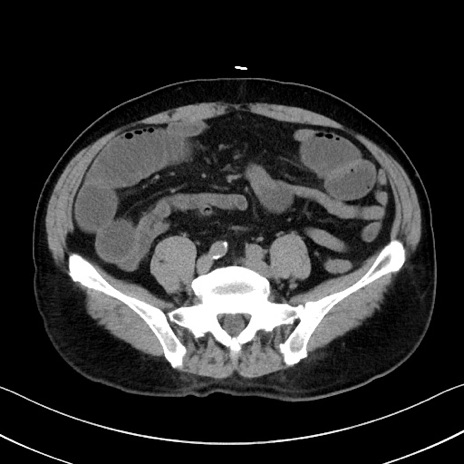

冠状断像

症例35(横断像)

【症例】70歳代 男性

【主訴】腹部膨満、嘔吐

【現病歴】昨日より腹部膨満感出現。本日増悪し、仙痛出現。嘔吐あり、受診。

【既往歴】糖尿病、胆摘後

【身体所見】BP 149/80mmHg、HR 74/min、BT 35.9℃、腹部:膨満、軟、圧痛なし。腸雑音減弱あり。上腹部正中切開瘢痕あり。

【データ】WBC 13500、CRP 1.72